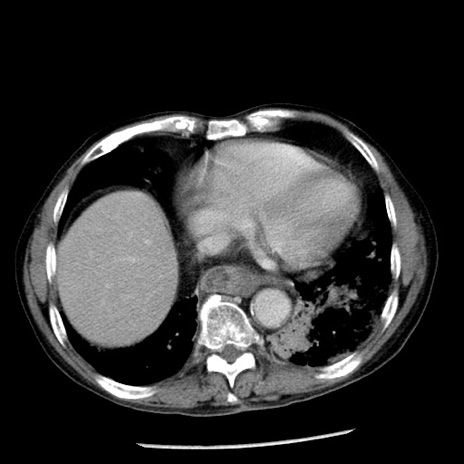

症例26(横断像)

【症例】80歳代男性

【主訴】嘔吐

【現病歴】昨晩2回嘔吐あり、今朝になっても嘔吐あり。来院。

【既往歴】胃潰瘍

【身体所見】意識清明、BT 37.6℃、BP 166/95mmHg、HR 100bpm、SpO2 97%、腹部:平坦・軟、腸蠕動音聴取良好、圧痛なし。

【データ】WBC 21900、CRP 1.46